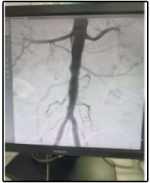

Case of aortic stenosis with both leg ulcers detected to have aortic occlusion treated with aortic stent graft system.

Before

After